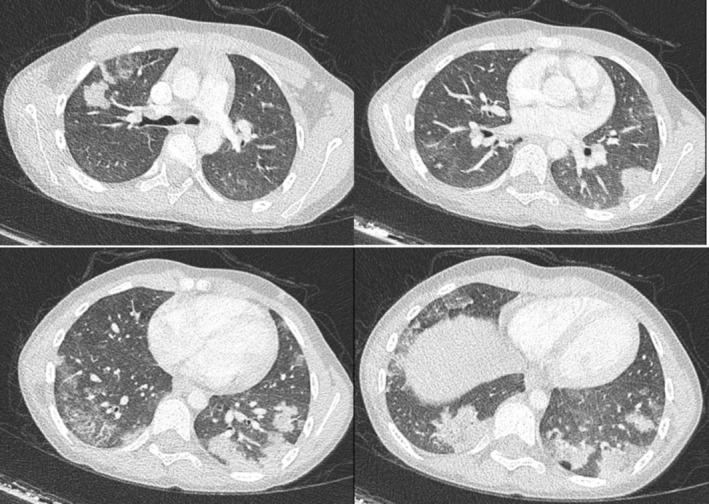

We report a case of a 6-year-old girl with IPH, who developed neuropsychiatric symptoms, including restlessness, confusion and myoclonic movements, after the therapeutic use of hydroxychloroquine.

我们报告1例6岁患IPH的女孩,在接受羟氯喹治疗后出现神经精神症状,包括烦躁不安、意识模糊和肌阵挛运动。